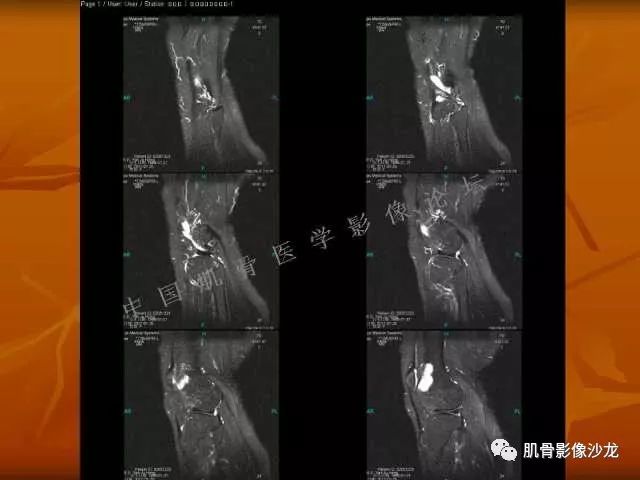

飞鹰行动 : 第一列可以看见T2小结节样高信号,周围有纤维组织环绕

高回青 : 另外还可以见到扇贝状分叶

2、软骨基质T2WI高信号,软骨小叶分叶状,也就会出现高老师提到的骨内膜扇贝形压迹。一般认为骨内膜扇贝形压迹超过骨皮质厚度的2/3是软骨肉瘤在长管状骨的特征性表现。如上图。3、软组织肿块或肿胀;

5、增强后进行性延迟,不均匀分割状强化, 会强化的纤维间隔,软骨小叶不会强化,关于老师们说到的钙化,软骨肉瘤不一定会有钙化 。